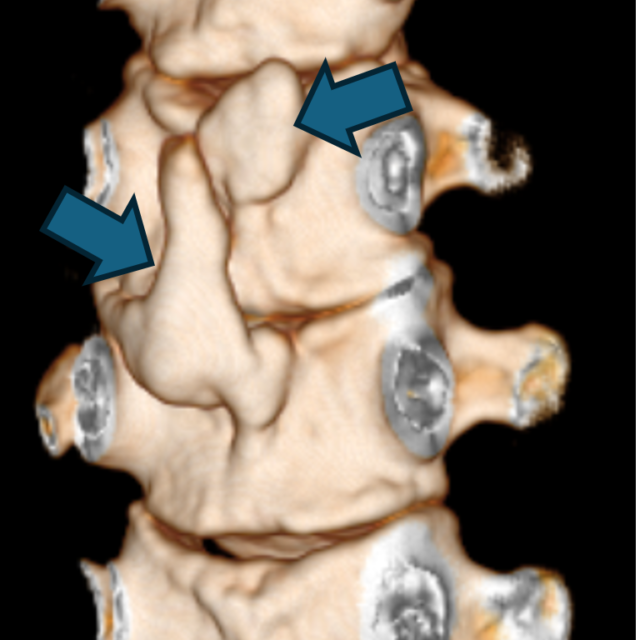

肋骨骨折と二分肋骨 Rib fracture&Bifid rib

みなさんこんにちは!​​​ ブログ担当技師です。​​​ ​​​ ​​​ 今回は肋…